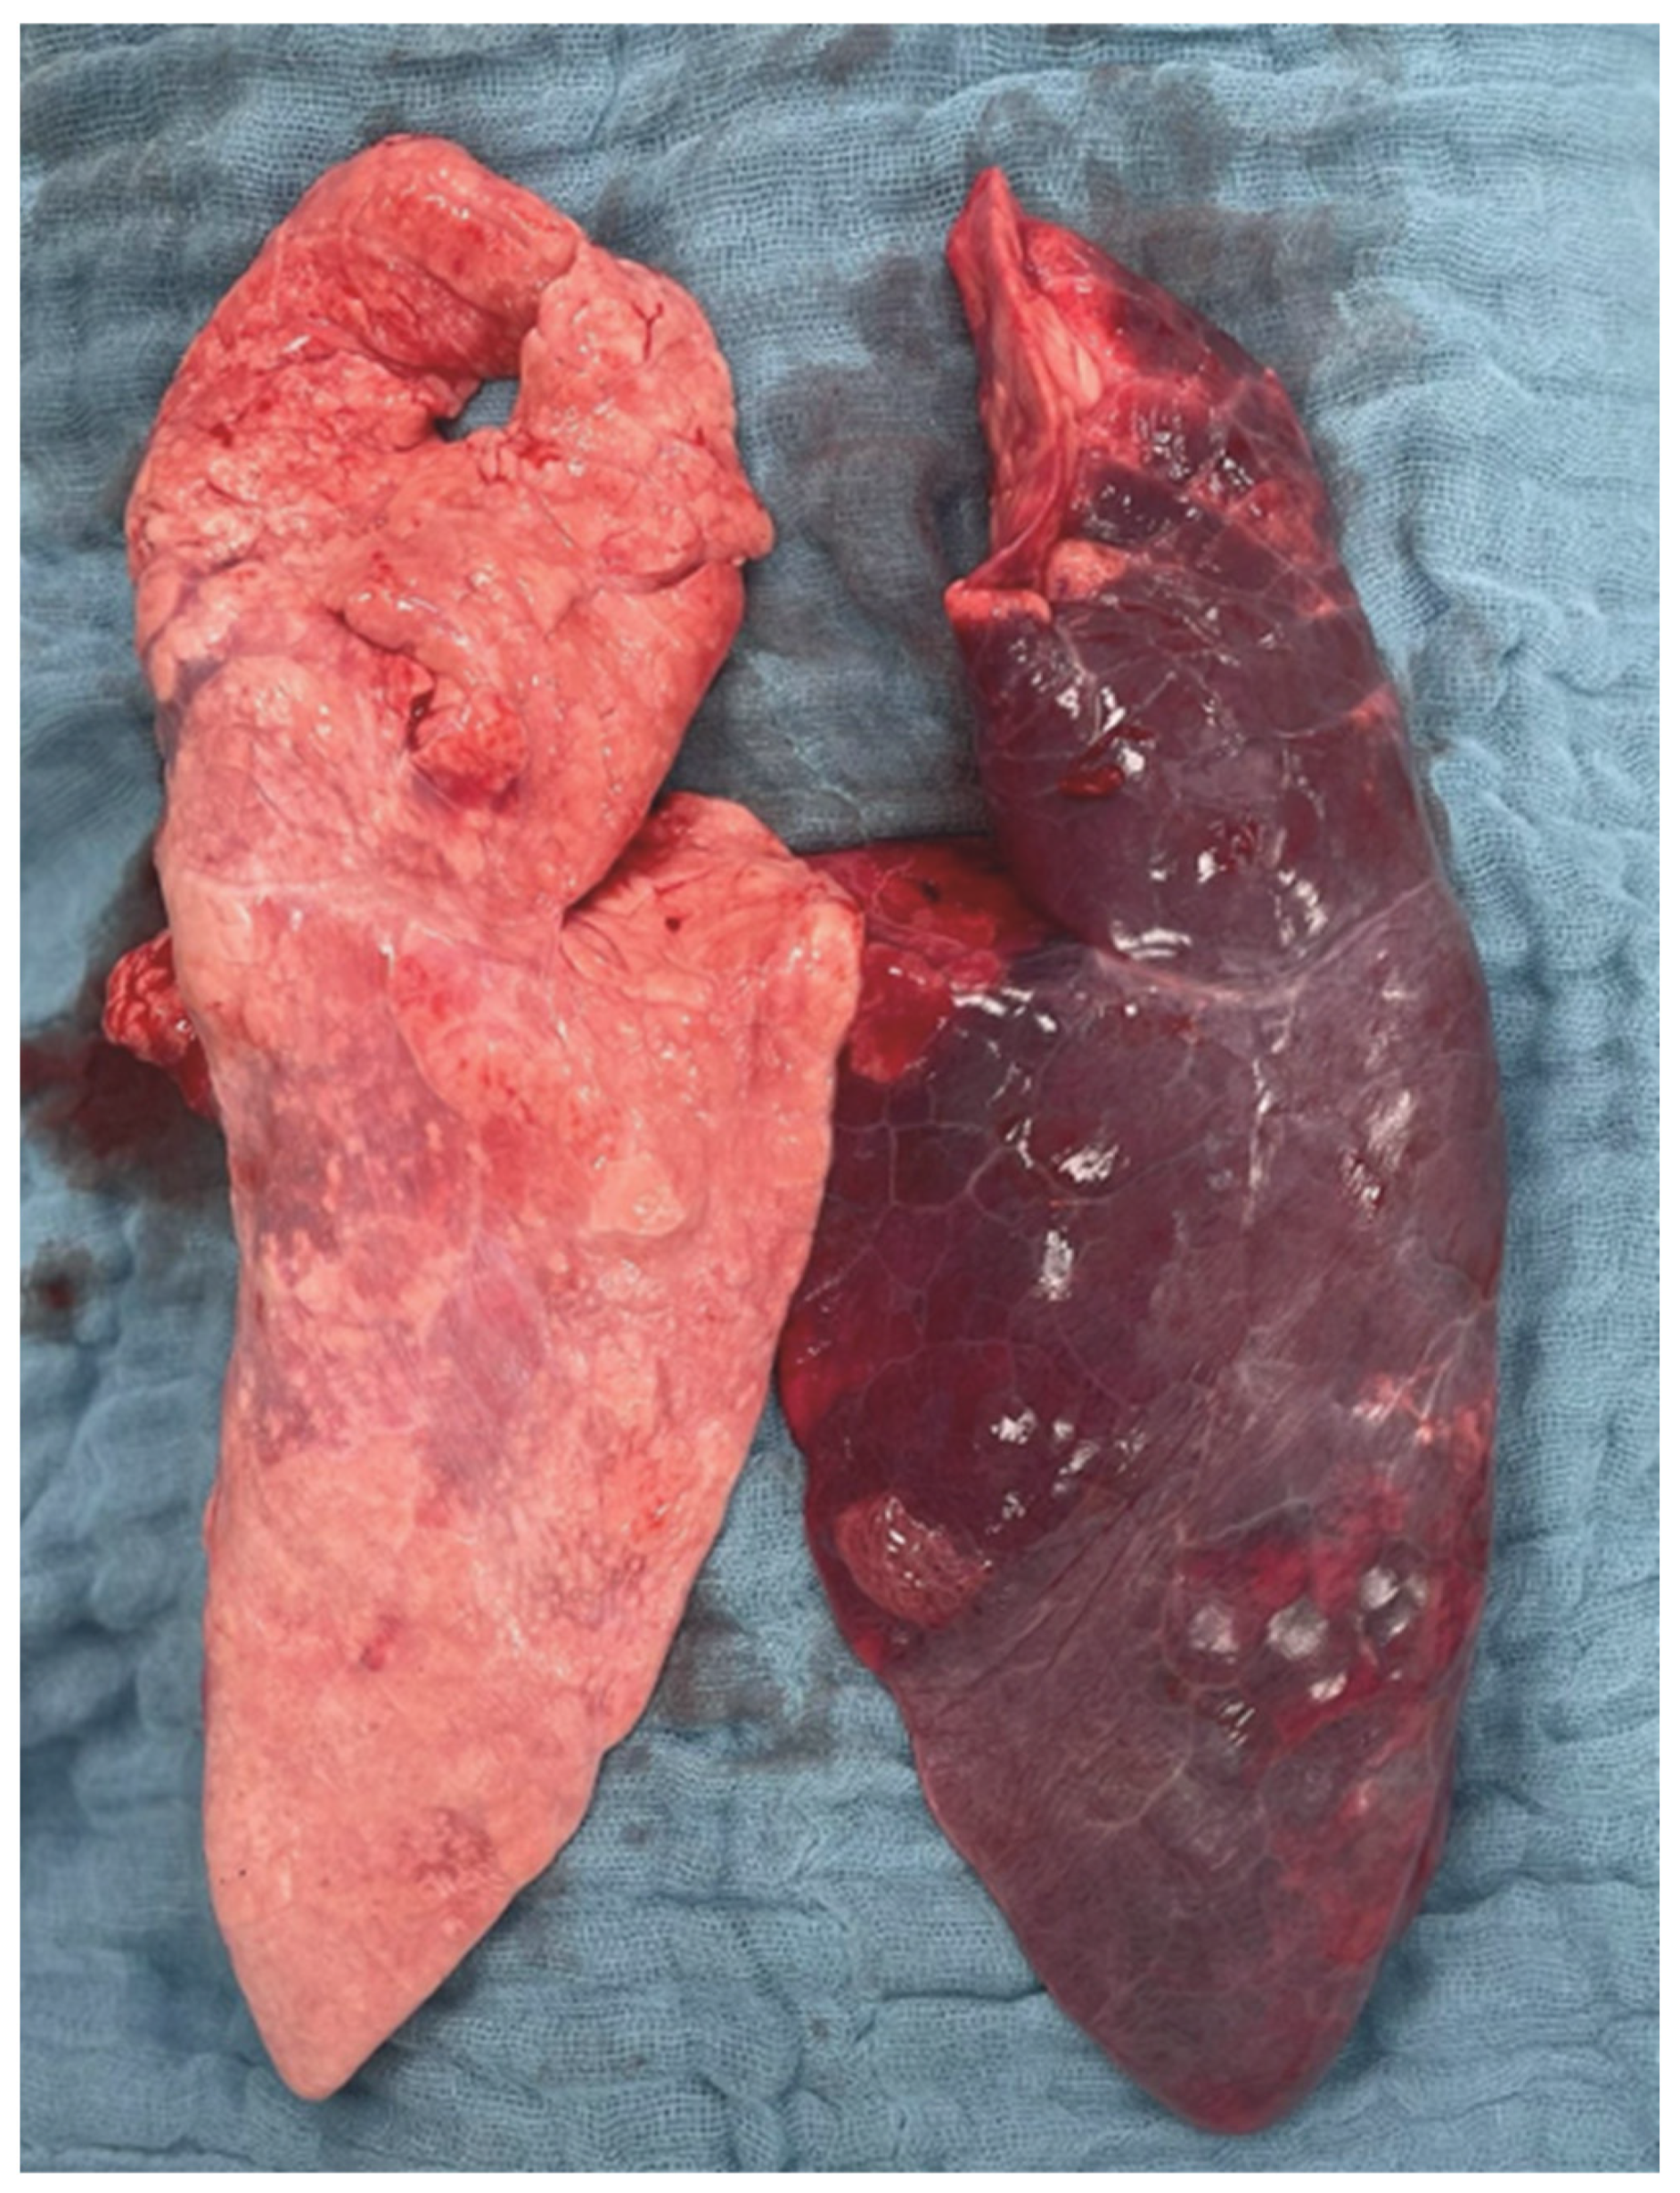

2.3. Histopathological Lung Injury Score

2.3.1. Left vs. Right Lung

2.3.2. Intergroup Differences

3.1. Experimental Model

3.4. Histopathological Findings

4.5. Experimental Protocol

4.9. Plasma Biomarker Profiling